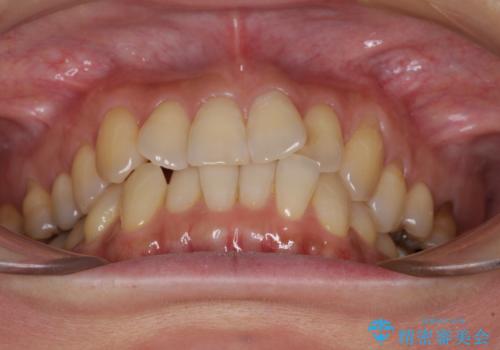

- 前歯のクロスバイトが気になり、インビザラインによる矯正治療を希望して来院された患者様です。

上顎側切歯(上の真ん中から2番目の歯)が舌側転位している場合、インビザラインでは仕上げきれないことが多く、更には無理して動かそうとすると歯髄壊死を起こすリスクが高いと言われています。

インビザラインで歯列を移動する前に、上顎前歯をワイヤー矯正で整え、その後上下歯列をインビザラインにて矯正治療を行うこととしました。

舌側転位している側切歯特有の、切縁の位置が不揃いであったり、根元が内側に引っ込んだ状態であったりという、インビザライン独特の仕上がりになることなく、きれいに整った歯列とすることができました。